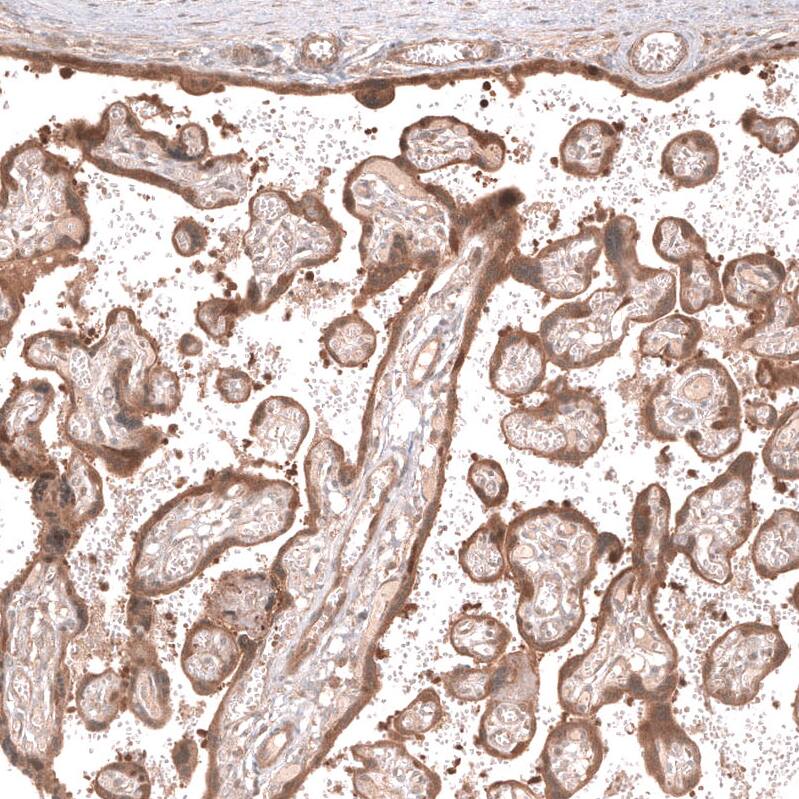

Immunohistochemistry-Paraffin: Lgr5/GPR49 Antibody (CL13579) [NBP3-24571]

Analysis in human placenta and tonsil tissues using NBP3-24571 antibody. Corresponding LGR5 RNA-seq data are presented for the same tissues.

Staining of human placenta shows moderate cytoplasmic and membranous positivity in trophoblastic cells.